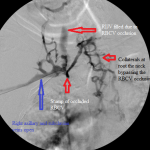

- Central venogram. Note numerous collaterals bypassing the occluded RBCV.

- Central venogram post-dilation of the RBCV: the venous collaterals are resolved.

I ran into a resistance in the mid right arm that I overcame and an obstruction behind the head of the right clavicle that stopped me in my tracks. I obtained pullback venogram that confirmed these to be due to a long critical stenosis of the mid right brachial vein, immediately distal to the anastomosis of the graft to the vein, and total chronic occlusion of the right brachiocephalic vein, respectively. The latter was associated with numerous ipsilateral and contralateral venous collaterals at the root of the neck as well as refluxing of radiocontrast up the right internal jugular vein.

Then I dilated the brachial venous stenosis and probed through and dilated the right brachiocephalic vein. The brachial venous dilation proved optimal, but there was residual stenosis of the RBCV that I resisted stenting at the same setting.

Though I considered the RBCV disease a threat to the access, I chose to observe the access over time and delay stenting the stenosis for the following reasons:

- The presence of collaterals associated with it suggested that it was not the immediate cause of the graft failure. The collaterals must have provided sufficient pathways of central venous return that allowed optimal venous flow through the graft and normal intra-graft pressure, critical elements in preventing acute graft thrombosis. The most proximate causes of failure of the graft were the juxta-anastomotic stenosis and the critical stenosis of the mid right brachial vein.

- There was no associated swelling of the right upper extremity after I restored function to the graft nor was there any when the patient returned for follow-up at my clinic, proving that the increased blood flow allowed by the plastied mid brachial vein stenosis and the juxta-anastomotic stenosis had sufficient pathways to return to the right atrium without elevating the intragraft pressure unduly.